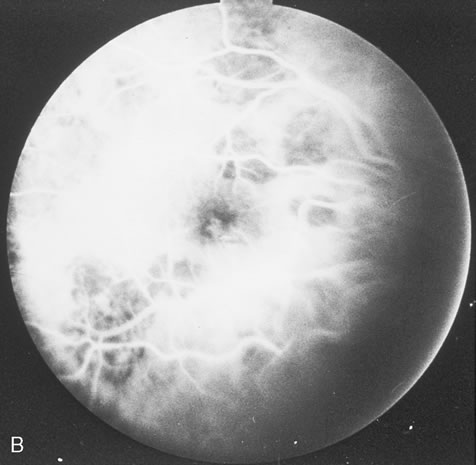

HIV infection results in depletion of T4 cells, which are central to various forms of immune responsiveness. Risk of developing AIDS is inversely related to the absolute T4 cell count. Antigen-responsive T cells become selectively depleted or functionally impaired early in the course of AIDS. There is diminished helper function for B-cell responses, depressed cytotoxic and natural killer cell responsiveness, decreased blast transformation, and decreased lymphokine production. Infected patients' B-lymphocytes spontaneously produce immunoglobulin, resulting in hypergammaglobulinemia, but are unable to produce specific antibody in response to new infections. Anergy is common. HIV also infects other cells that express the CD4 antigen, such as monocytes and macrophages, but is not cytopathic in these cells. HIV has been identified in brain capillary endothelium, oligodendrocytes, astrocytes, lymph node dendritic cells, Langerhans' cells, intestinal mucosa, myocardium, tears, corneal epithelium, aqueous, vitreous, and retina. Clinical manifestations of HIV are protean. Seropositive persons may be asymptomatic. Various acute HIV infection syndromes have been described. An acute mononucleosis-like syndrome, with fever, malaise, rash, lymphadenopathy, pharyngitis, myalgias, and arthralgias, has been noted after recent HIV exposure. Acute neurologic manifestations resembling aseptic meningitis, encephalitis, or focal lesions may be seen.25 AIDS-related complex is a somewhat ambiguous term encompassing features such as chronic fever, night sweats, weight loss, fatigue, generalized lymphadenopathy, chronic diarrhea, and laboratory abnormalities. AIDS-related complex implies an intermediate stage in the spectrum of HIV disease. CDC-defined indicator diseases include HIV encephalopathy, HIV wasting syndrome, CMV disease not involving liver, spleen or lymph nodes (26), progressive multifocal leukoencephalopathy, recurrent Salmonella septicemia, multiple or recurrent serious bacterial infections in children, extrapulmonary myobacterial infection, disseminated histoplasmosis, disseminated coccidioidomycosis, chronic isosporiasis, lymphoid interstitial pneumonia or pulmonary lymphoid hyperplasia in children, primary brain lymphoma, and various non-T–cell non-Hodgkin's lymphomas. Less specifically associated with HIV infection are manifestations of papillomavirus, molluscum contagiosum, VZV, Epstein-Barr virus, hepatitis B virus, chlamydia, gonorrhea, syphilis, campylobacter, pityrosporum, trichophyton, aspergillus, acanthamoeba, entamoeba, giardia, strongyloides, basal cell carcinoma, squamous cell carcinoma, idiopathic thrombocytopenic purpura, cerebrovascular infarction, and intracranial hemorrhage.27–30 Pneumocystis carinii pneumonia once was the most common presentation of AIDS. It is typically of insidious onset, with features including dry cough, dyspnea, and a diffuse bilateral interstitial infiltrate evident on a chest roentgenogram. Typical multifocal fundus lesions have been described. They are yellow-white and have a characteristic pattern on fluorescein angiography (Fig. 10A, 10B, and 10C). Diagnosis is made by demonstrating the protozoon via sputum induction, bronchioalveolar lavage, and transbronchial or open-lung biopsies. Treatment modalities include trimethoprim-sulfamethoxazole (TMP-SMX).31 Kaposi's sarcoma is much more frequent in male homosexuals and bisexuals than in other patients with AIDS. Cutaneous lesions are usually red or violaceous, palpable, and nonblanching papules, nodules, or plaques, often appearing on the hard palate, nose, eyelid, and conjunctiva (Fig. 11). Visceral and lymph node involvement is common and often clinically silent. Biopsy specimens show proliferation of small, incompletely formed blood vessels lined by unusually large endothelial type cells, with extravasated red blood cells and infiltrates of spindle-shaped cells. Chemotherapy with etoposide, Vinca alkaloids, or interferon-α may be indicated in advanced cases.28